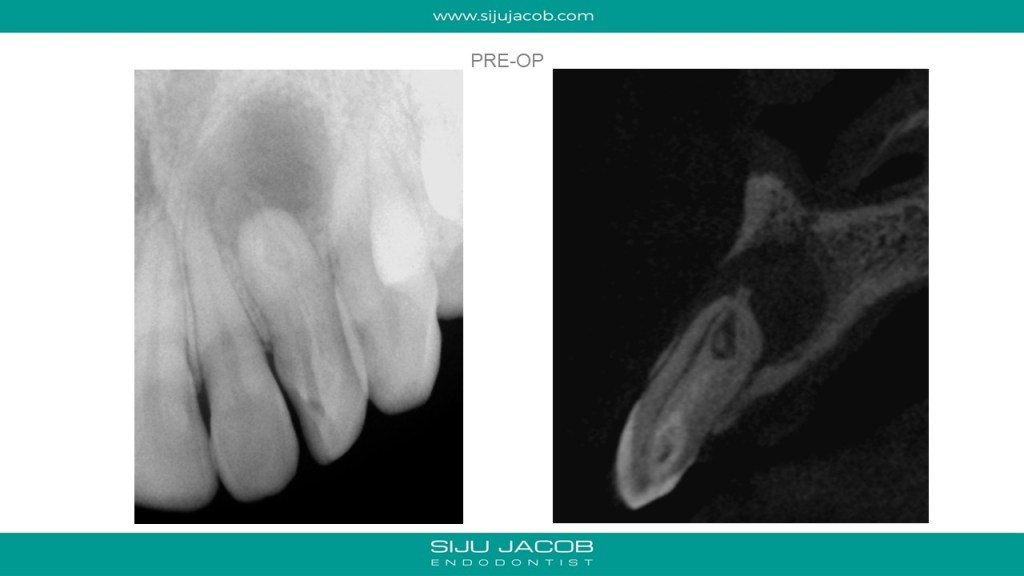

This case was done in single visit. The patient was the brother of an Endodontist and flew in from Hyderabad for treatment. I did the orthograde endo followed by immediate apical surgery. In the orthograde part, I filled the Dens tract and the canal. I then raised a flap, resected the apical part to expose the “pouch” of the dens. I used a pear shaped ultrasonic tip to clean the pouch and packed it with MTA. The patient flew back the same day and got the sutures removed in Hyderabad. A colleague, (Dr. Pavan Nallapati) send me a recall radiograph. At the 3 year recall, it seems to have healed and doing well. In hindsight, I felt i hurried through the orthograde part. when treating these cases, we inevitably leave behind a lot of anatomy untouched. I’m also thinking whether i can do these cases just surgically and leave the orthograde part as it is. I might do that the next time.